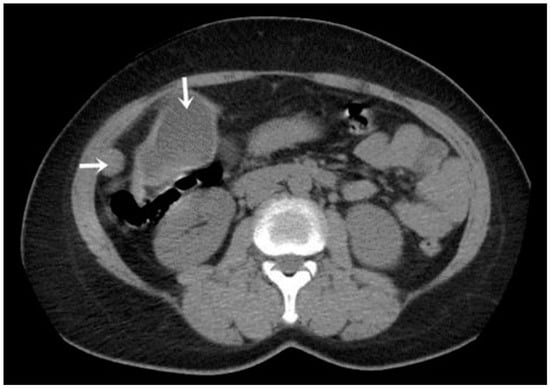

A CT examination revealed multiple cystic images in the hepatic segments V, VI, and VII, with subhepatic extension and involvement at the fissures of the venous ligament. Cystic images were also observed in the anterior abdominal wall and submesocolic (Figure 5, Figure 6, Figure 7, Figure 8 and Figure 9). Blood tests showed no significant abnormalities, and ELISA determination of IgG class antibodies to Echinococcus granulosus was positive at 1.66 IV (with values considered negative at ≤0.9 IV and positive at ≥1.1 IV).

The imaging highlights hepatic cysts in segments V, VI, and VII, a large cystic formation in the round ligament, a cyst in the parietal peritoneum, two cysts in the greater omentum, and two cysts located in the submesocolic enteral mesentery.

Figure 4. Peritoneal and segment V cyst (indicated by arrows).